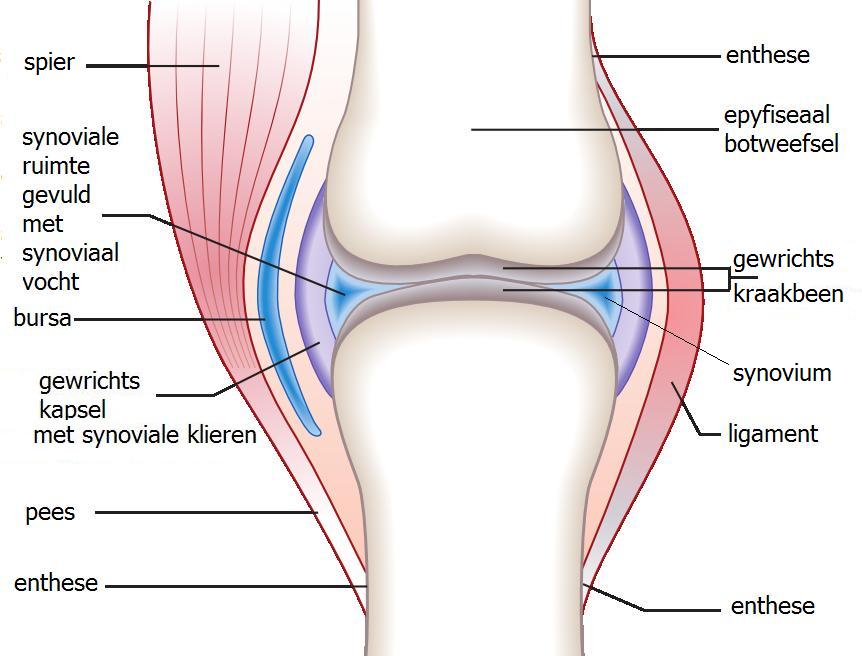

Een gewricht is een verbinding tussen twee botten waarin beweging mogelijk is. In het lichaam bevinden zich grotere gewrichten, zoals de schouders en heupen maar ook kleinere gewrichten zoals de gewrichtjes in de handen, voeten en tussen de ruggenwervels.

Er zijn ook veel verschillende soorten gewrichten, die elk andere bewegingen kunnen maken. Zo kan een knie buigen en strekken (scharniergewricht) en kan een schouder alle kanten op bewegen (kogelgewricht). Dit zijn beide voorbeelden van een synoviaal gewricht. Kenmerkend voor deze gewrichten is dat er een gewrichtsholte aanwezig is die gevuld is met een stroperige vloeistof (synoviale vloeistof). De botuiteinden zijn bedekt met kraakbeen en het gewricht wordt bij elkaar gehouden door omliggende structuren, die bestaan uit een kapsel, banden, spieren en pezen.

Afbeelding 1. De opbouw van een (synoviaal) gewricht

Bron: Wikipedia.